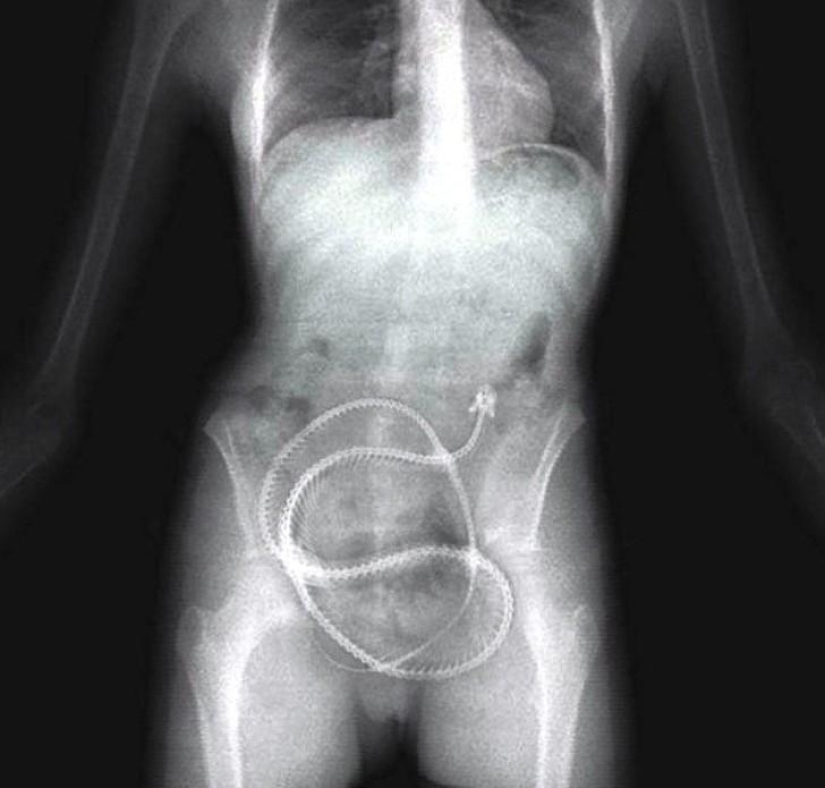

Muelles de cama.